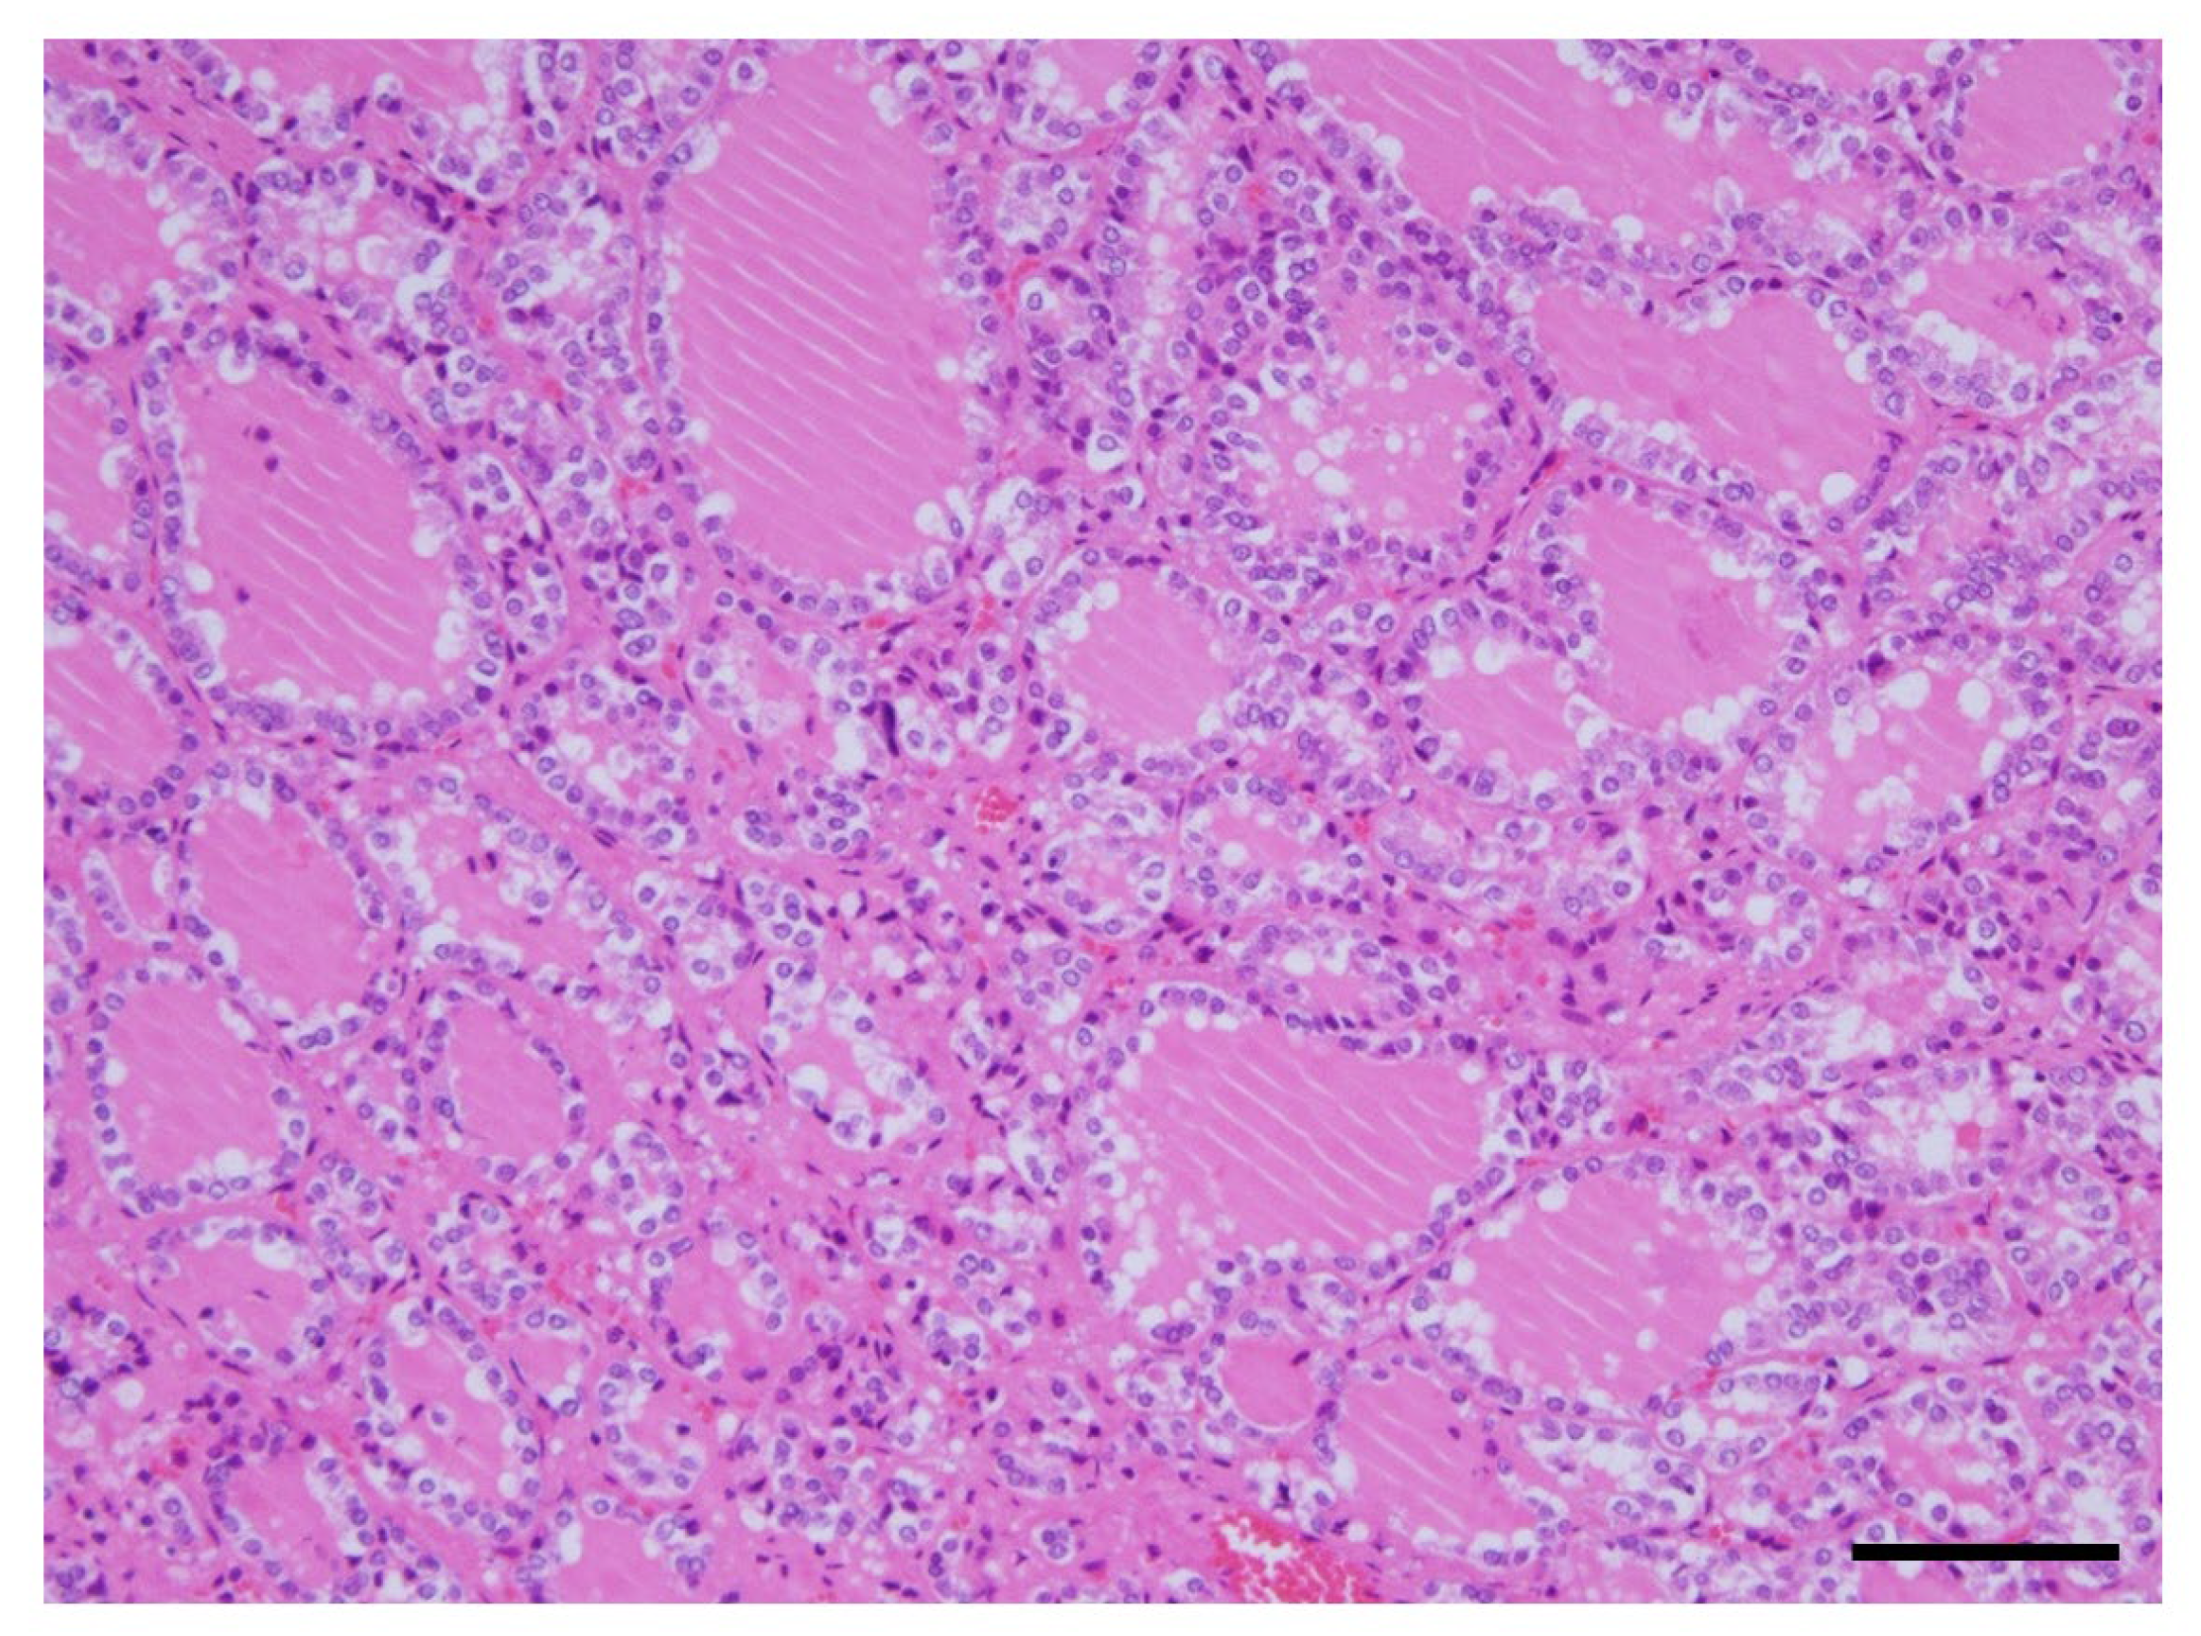

The histological findings of the thyroid gland showed increased thyroid follicle growth and increased colloidal resorption, suggesting a hyperthyroid state (Figure 5).

Figure 5.

Histological findings of the thyroid gland. The image of an adenomatous goiter was presented. No malignant findings were observed. This showed increased thyroid follicle growth and increased colloidal resorption, suggesting a hyperthyroid state. Scale, 100 µm. HE staining.